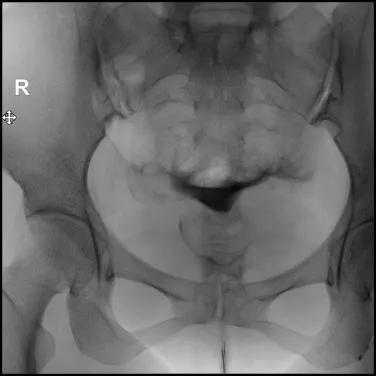

9.在注入对比剂后的20分钟或24小时再拍一张弥散片,观察对比剂在盆腔的弥散情况,分析宫颈、子宫、输卵管的形态特征;

弥散片